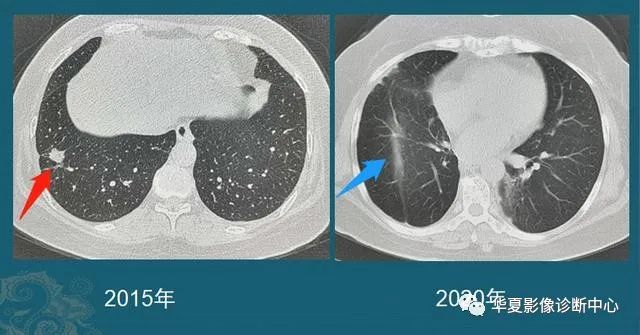

还有一种,随访过程中逐渐增大的肺结节,不论磨玻璃还是实性结节,都要重视!

绝大多数早期肺癌生长缓慢,对无法定性的肺结节,定期复查是个很实用的办法,可以避免过度医疗,也防止漏诊。

豪大夫每年都能发现很多从肺小结节长大的肺癌,挑出两个速度最快的分享一下:

图6

这位病人2016年体检还是正常的,2017年查出一个3 mm的肺结节,用了两年半时间,增长到>1 cm,手术病理是肺腺癌。

注意:这几乎是最快的一类的,很少见!所以高危人群推荐每年胸部体检一次是有益的。

图7

这是一位老年男性,有吸烟史,也是在两年多的时间内,肺结节从不足3 mm长到1 cm以上,后来病理确诊肺鳞癌。

中老年人定期胸部CT体检,可以及时发现这些生长较快的恶性肺结节,予以手术根治。